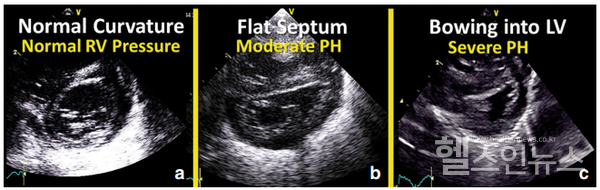

폐동맥고혈압의 정확한 진단 방법은 우심도자를 통해 폐동맥 압력을 측정하는 것이다. 하지만 신생아의 경우 이러한 침습적인 검사를 시행하기 어려워 심초음파 검사를 통해 진단하게 된다. 심초음파 검사에서 삼첨판 역류의 최고 속도가 2.8m/sec 이상일 때 의심, 3.2m/sec 이상일 확진할 수 있다. 또한 난원공이나 심방중격결손, 동맥관을 통한 우-좌 단락(혹은 양방향 단락)을 확인할 수 있고, 심실 중격의 좌심실로의 치우침과 그 정도를 확인해야 한다.